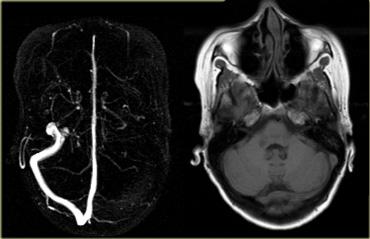

Ở ngoài cùng bên trái là hình MRA cho thấy không quan sát thấy xoang ngang trái.

Do giải phẫu tĩnh mạch có nhiều biến thể, điều này có thể do xoang ngang bị thiếu bẩm sinh hoặc do huyết khối.

Hình ảnh chuỗi xung T1W bên phải cho thấy rõ ràng rằng xoang ngang trái vẫn tồn tại, do đó các phát hiện trên MRA là do huyết khối.

Tiếp tục xem các hình ảnh tiếp theo.